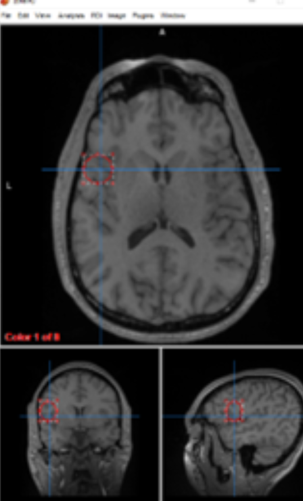

white matter

communication